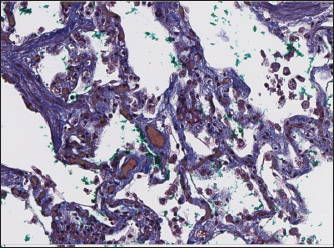

Immunohistochemical labeling with anti-CD31 antibody and anti-factor von Willebrand antibody showed wide dispersion between the groups. In the RHF group, we found a weak-to-absent reaction for the CD31 marker in most of the fibrotic fields, restricted to endothelial cells. Additionally, we discovered an intensive reaction to von Willebrand factor in most arterioles and in vessels with plexiform morphology. In sPCH animals, we observed significant expression of CD31 marker covering most of the fields and actively present in alveolar septae with numerous capillaries. However, the representation of von Willebrand factor was almost absent (Figs. 6 and 7).

Fig. 6. RHF group. Immunohistochemistry. Left top right top, left bottom—factor von Willebrand active expression on endothelial surface in pulmonary vessels. Right bottom—absence of reaction on CD31 marker of endothelial cells.

Fig. 7. sPCH group. Immunohistochemistry. Left—active expression of CD31 marker in numerous endothelial cells in alveolar septae. Right—almost absent of factor von Willebrand expression in cells.